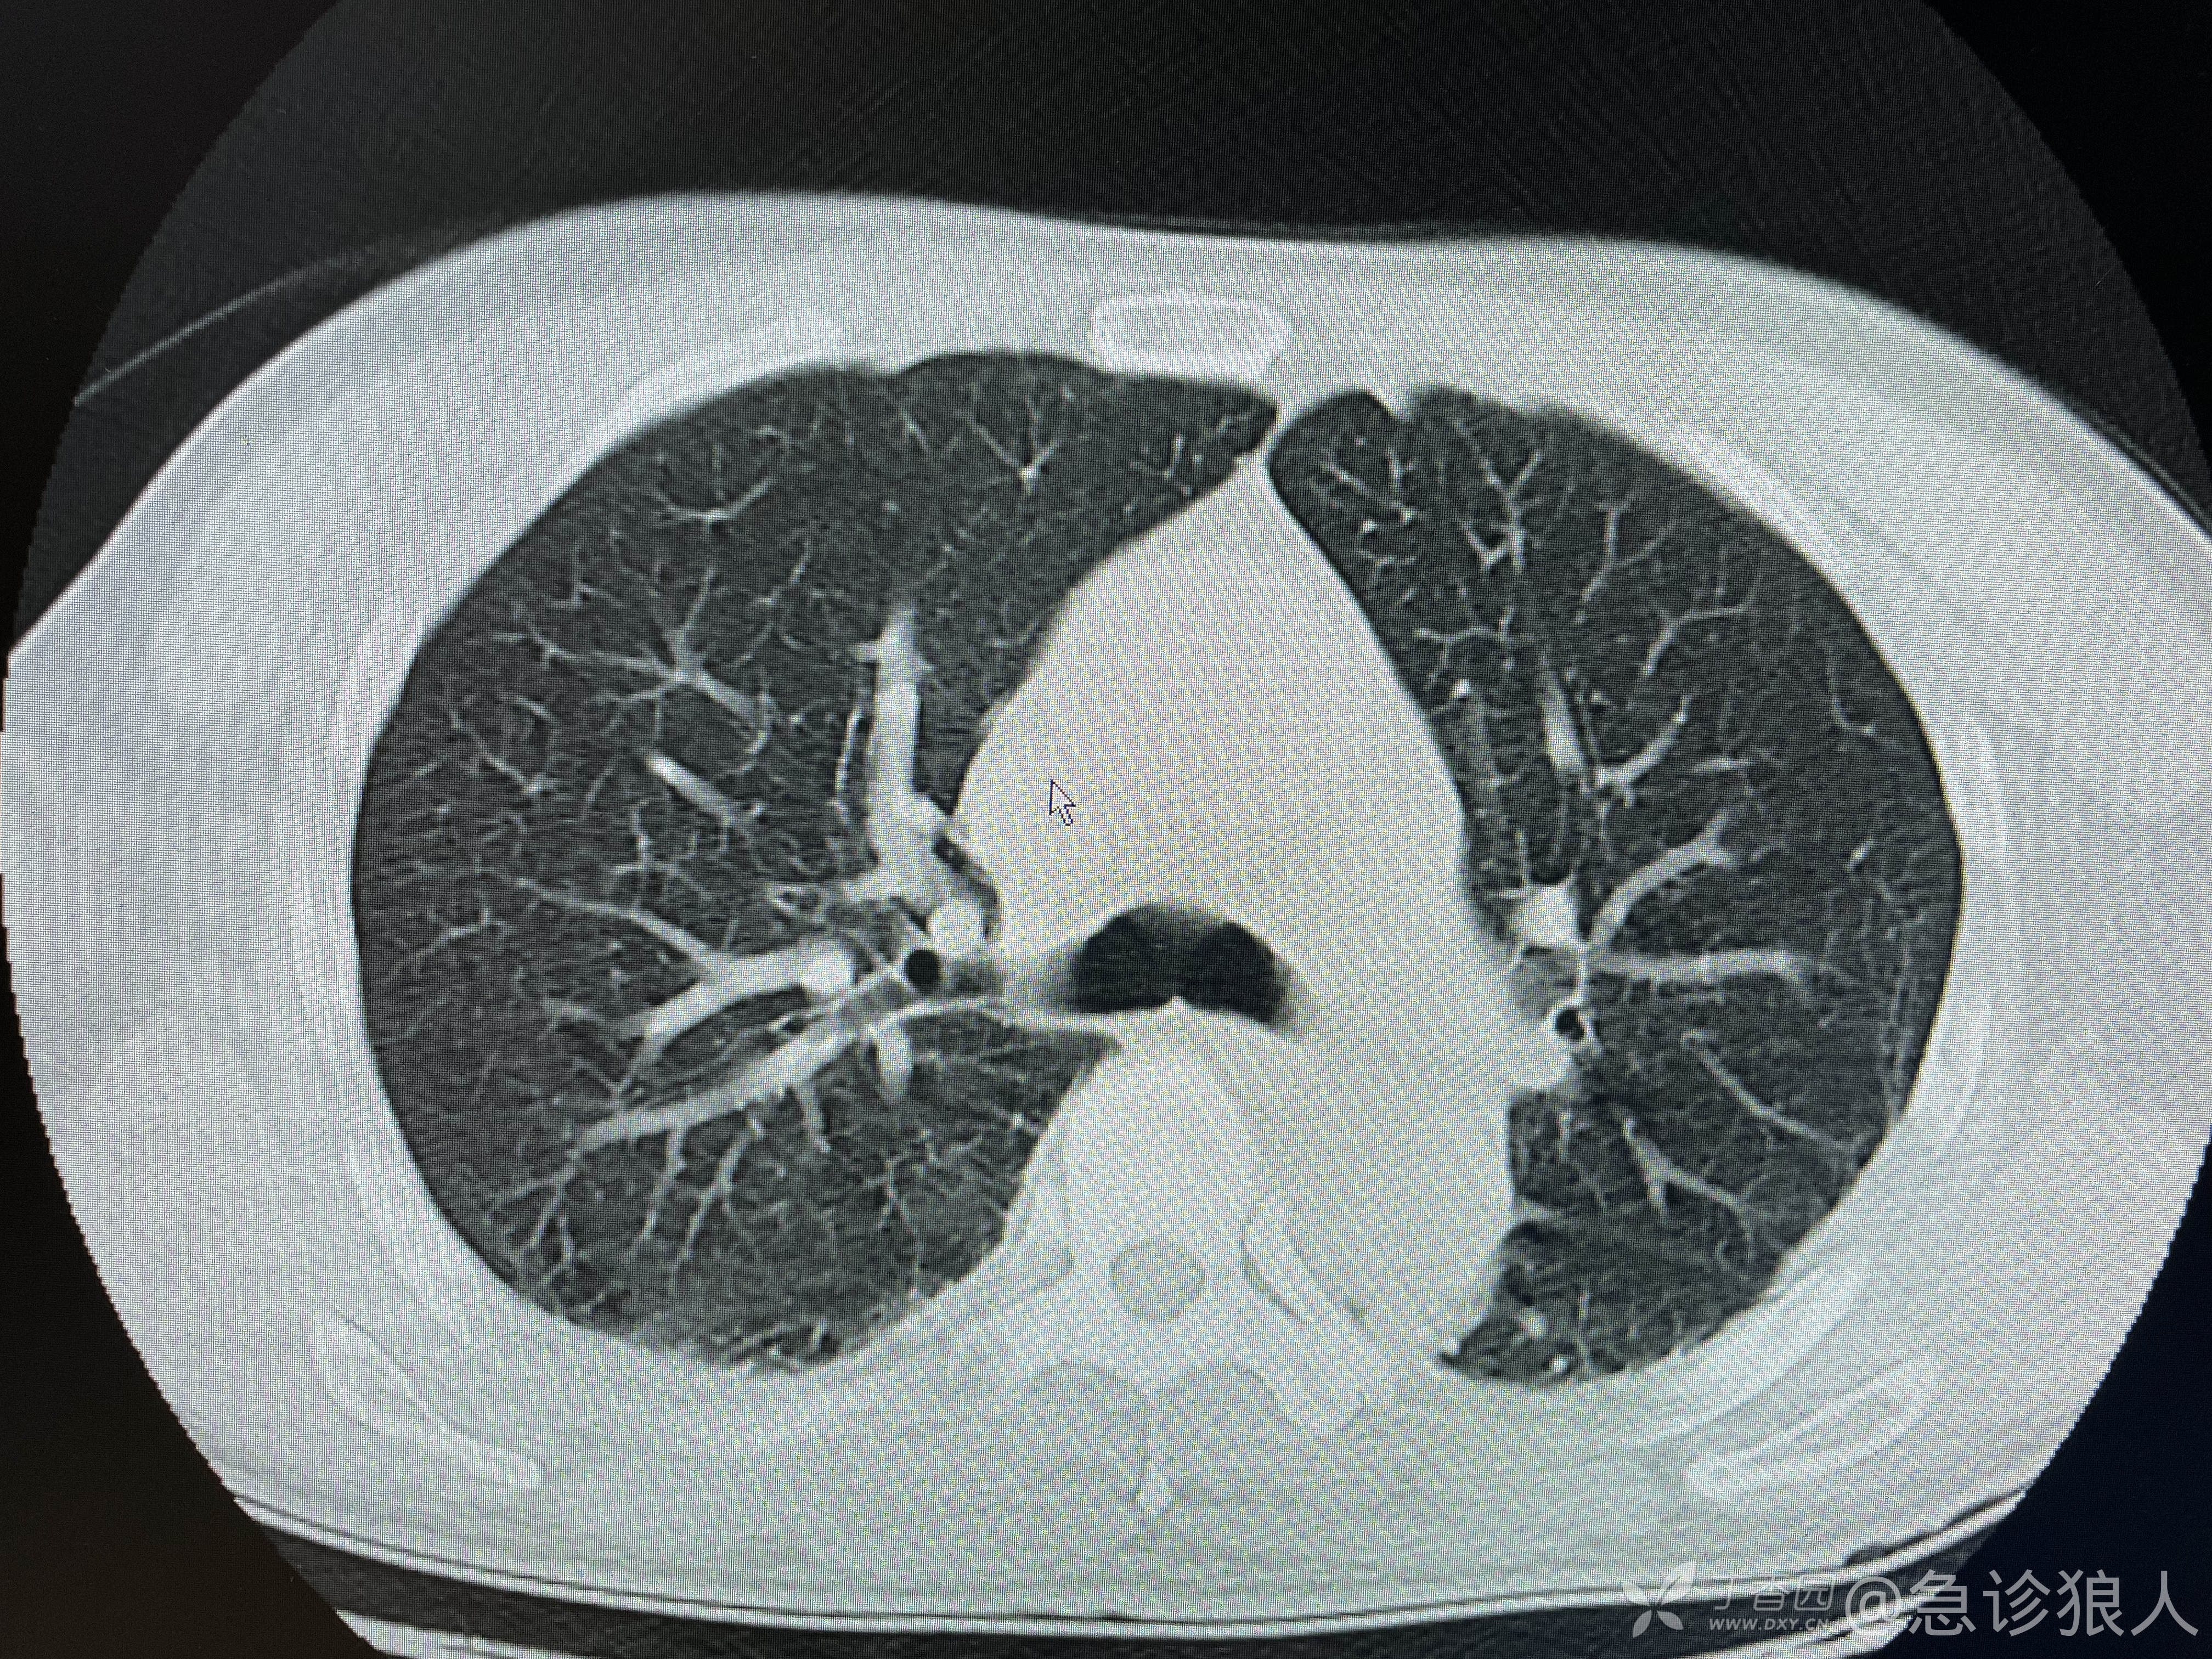

可是ct如下:

看完ct,什么感觉?

脑内软化灶,有点时间了,肾周渗出,可能是新的!